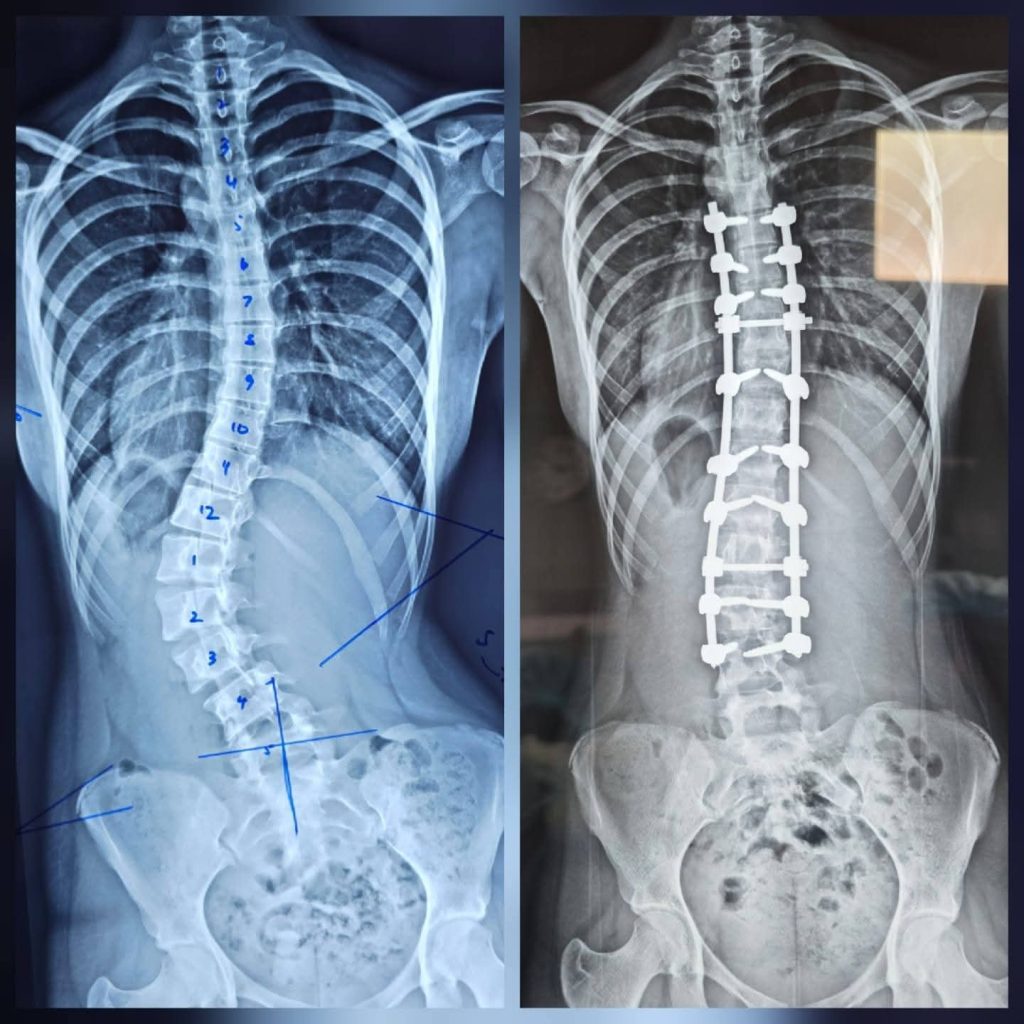

புத்தளம் தள வைத்தியசாலையில் முதன் முறையாக முள்ளந்தண்டு நேராக்கல் (Scoliosis Correction) சத்திர சிகிச்சை இடம்பெற்றது

புத்தளம் தள வைத்தியசாலையில் முதன் முறையாக இடம்பெற்ற முள்ளந்தண்டு நேராக்கல் (Scoliosis Correction) சத்திரசிகிச்சை வெற்றிகரமாக மேற்கொள்ளப்பட்டுள்ளது.

கடந்த சில மாதங்களாக முள்ளந்தண்டு சத்திர சிகிச்சைகள் இங்கு இடம்பெற்றுவந்தபோதிலும் முள்ளந்தண்டு நேராக்கல் (Scoliosis Correction) சத்திர சிகிச்சை, புத்தளம் தள வைத்தியசாலையில் மேற்கொள்ளப்பட்ட முதலாவது சந்தர்ப்பம் இதுவாகும்.

என்பு முறிவு விசேட வைத்திய நிபுணர் ஷெஸார் ஹமீத் தலைமையில் இடம்பெற்ற இந்த சத்திர சிகிச்சைக்கு, சிரேஷ்ட என்பு முறிவு விசேட வைத்திய நிபுணர்களான தேசிய வைத்தியசாலையை சேர்ந்த டாக்டர் உதை டி சில்வா மற்றும் லேடி ரிஜ்வே வைத்தியசாலையின் டாக்டர் நிர்மல் மாரசிங்ஹ ஆகியோரும் வருகை தந்திருந்தனர்.

40 லட்சம் ரூபாவுக்கும் அதிகம் செலவாகும் இந்த சிகிச்சை முற்றிலும் இலவசமாக மேற்கொள்ளப்பட்டுள்ளது.

இலங்கையில் உள்ள தளவைத்தியசாலைகளில் (Base Hospitals) இதுவரை இந்த சத்திர சிகிசிச்சை மேற்கொள்ளப்படவில்லை என்பதும் சுட்டிக்காட்டத்தக்கது.